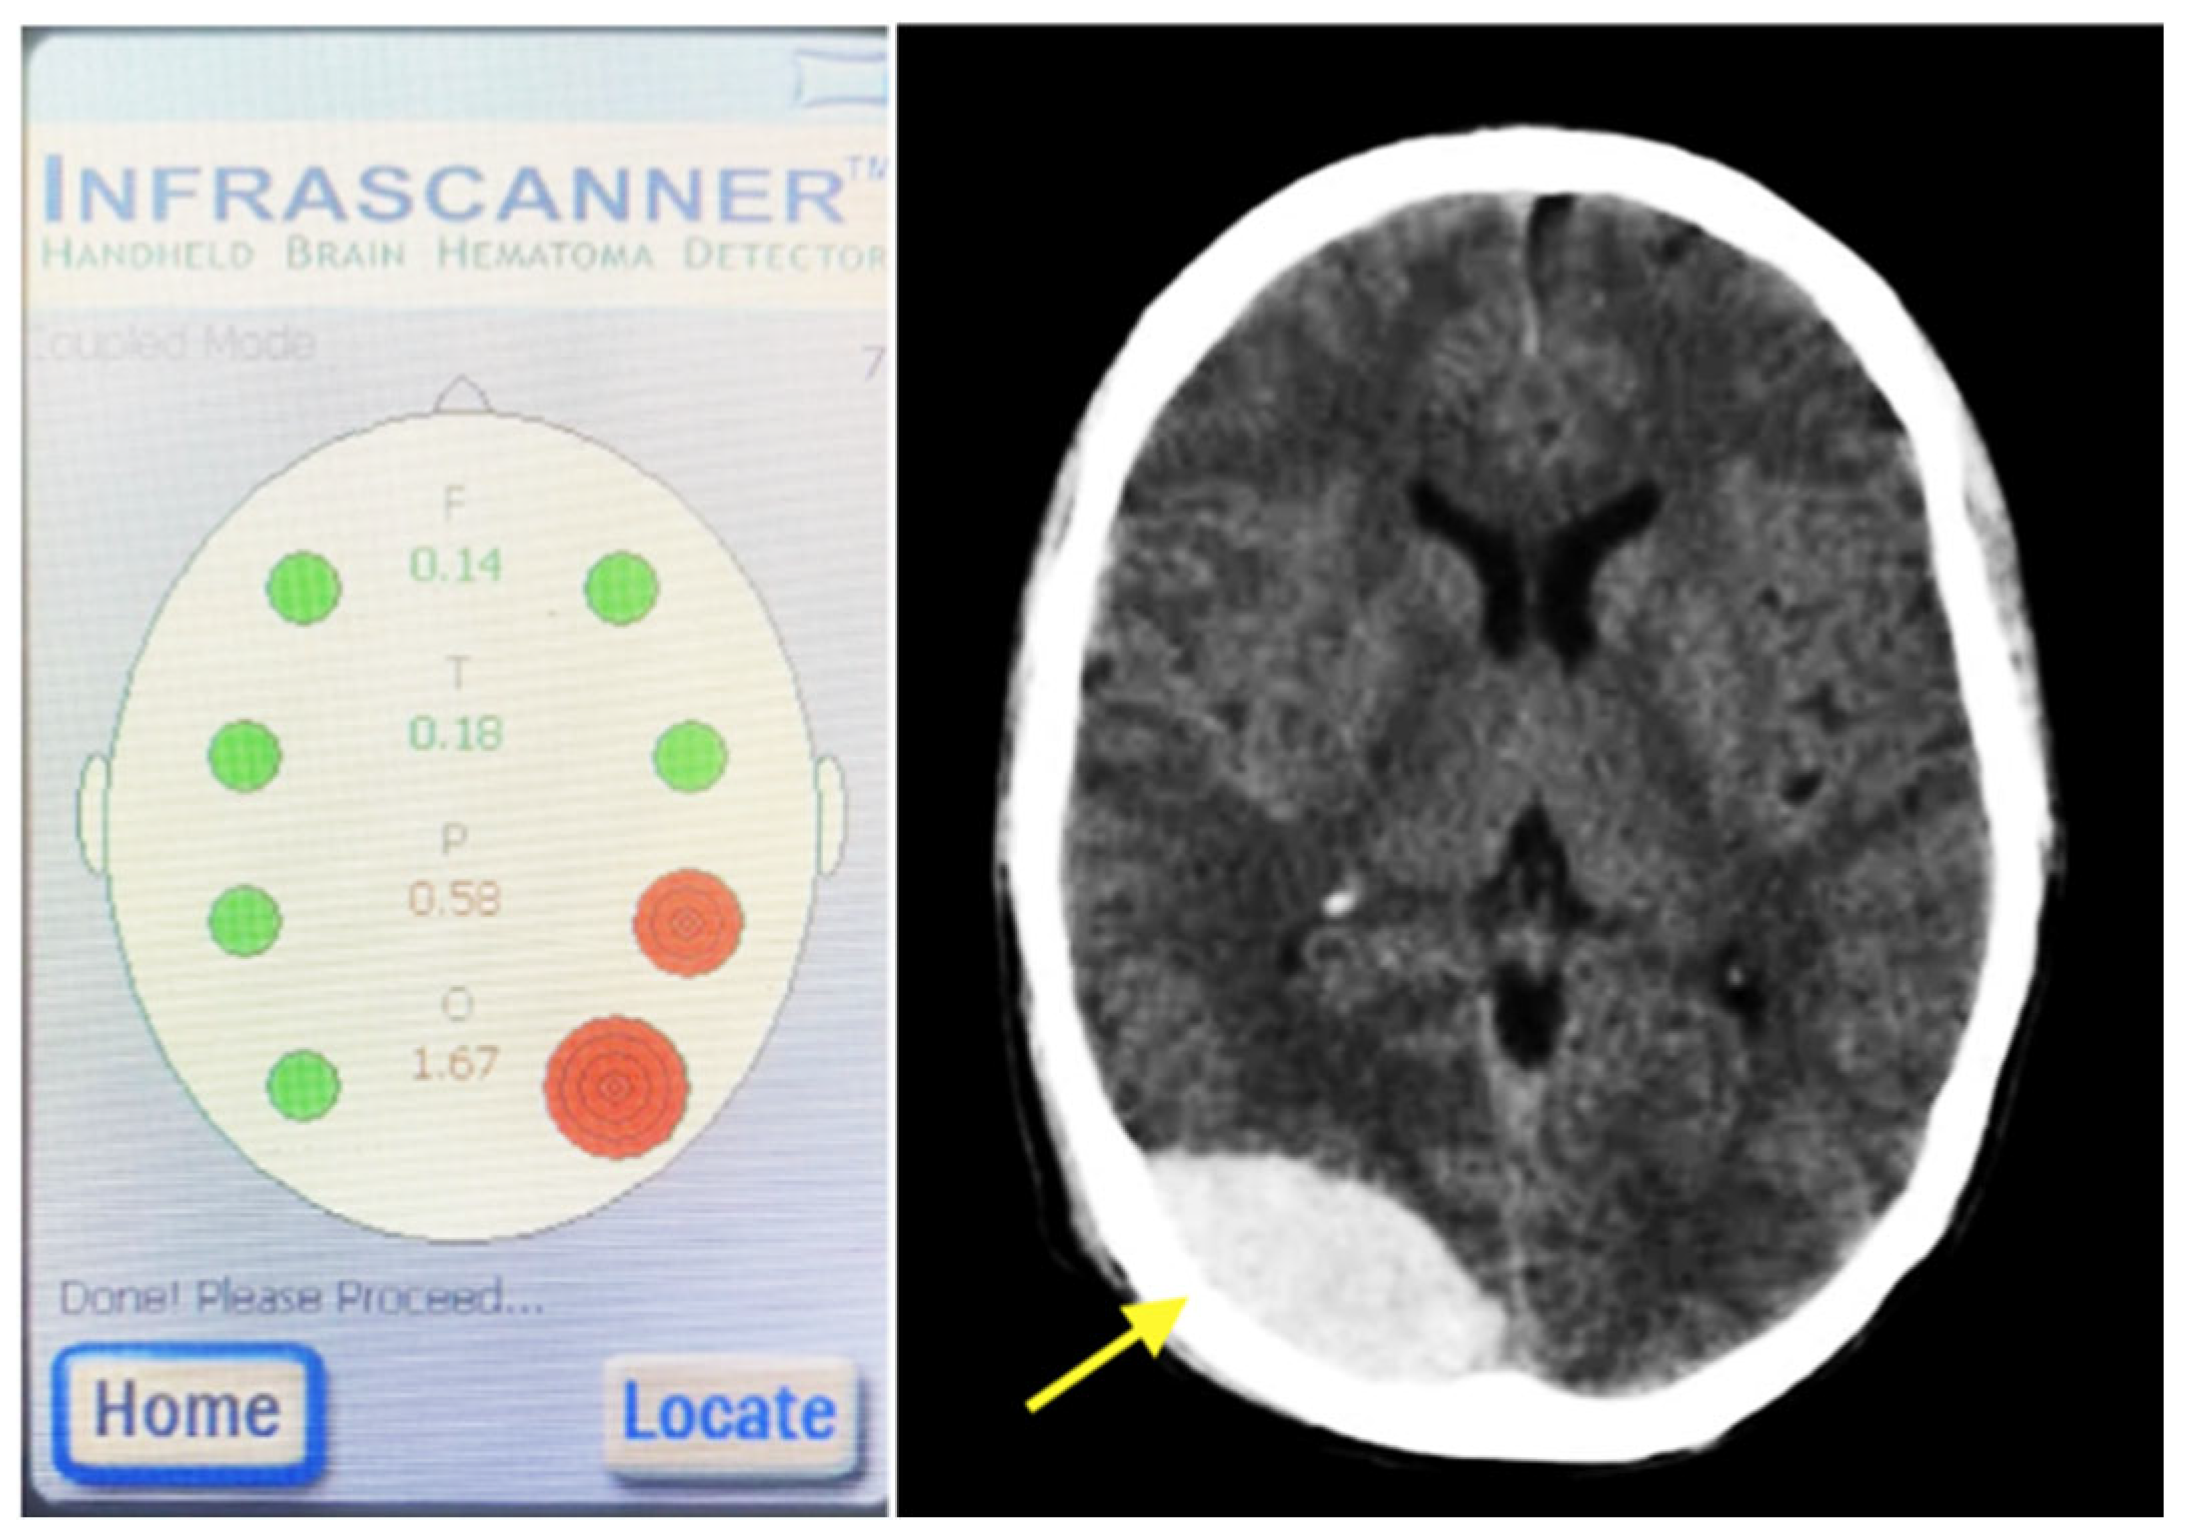

- NIRS measurements were performed in the emergency department according to the device’s user manual, and the resulting data were recorded (Figure 2).